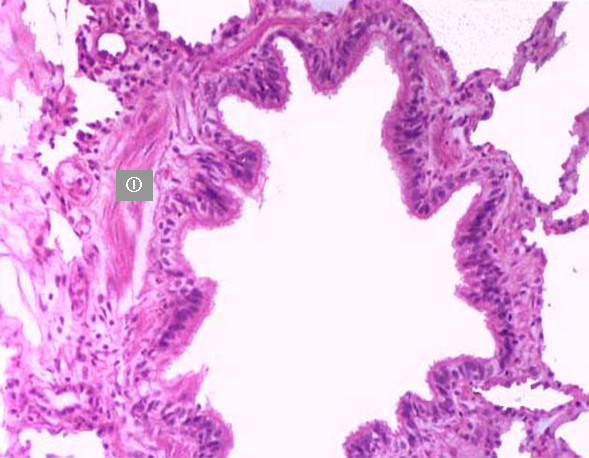

2、细支气管

① 上皮逐渐变为单层纤毛柱状上皮,杯状细胞很少或消失;

② 腺体少或消失;

③ 软骨片少或消失;

④ 环行平滑肌完整成层,黏膜形成皱襞。

细支气管 细支气管光镜图

1.单层纤毛柱状上皮 2.软骨片 3.平滑肌束 4.肺泡 ①平滑肌束